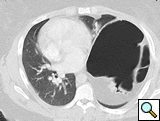

Because of the extreme diaphragmatic elevation an open approach through the chest was selected for correction of the abnormality. After preoperative bowel preparation, the patient was taken to the operating room and a muscle-sparing left antero-lateral thoracotomy was performed in the 5th intercostal space. With this approach the free edge of the latissimus dorsi is mobilized posteriorly and the serratus anterior is freed up at the level of its anterior insertion on the chest wall, allowing easier access to the anterior portion of the diaphragmatic leaflet. The diaphragm appeared morphologically normal but relaxed (Figure 3).